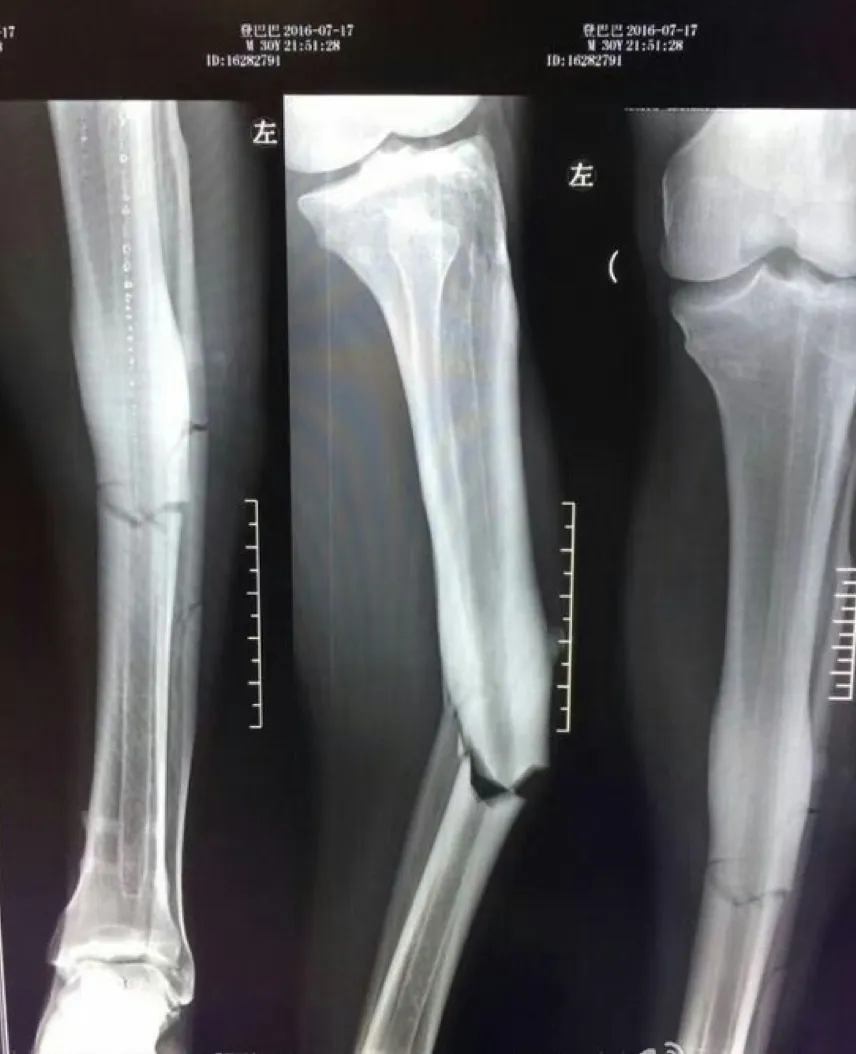

Trước mắt, theo thông báo của bác sỹ từ kết quả chụp X quang, Demba Ba sẽ phải nghỉ thi đấu ít nhất 8 - 10 tháng để vết thương lành hẳn. Nhìn vào tấm hình phim X-quang chụp vết thương của cầu thủ 31 tuổi sẽ khiến không ít người rợn người. Ống quyển của Demba Ba gần như gãy vụn trong tai nạn vừa qua.

Tấm phim X Quang cho thấy xương chân gãy vụn